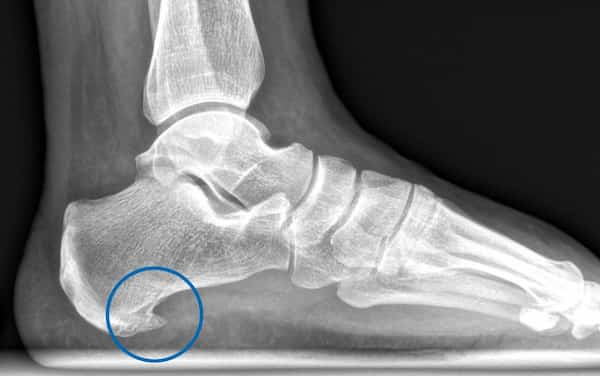

Las plantillas a medida son un tratamiento eficaz para aliviar dolores de pies, rodillas, caderas e incluso espalda. Sin embargo, no basta con hacer unas simples plantillas biomecánicas: un diagnóstico incompleto puede provocar nuevas descompensaciones en otras partes del cuerpo.

En nuestra clínica realizamos una exploración biomecánica muy completa, valorando no solo la pisada, sino también cómo se relaciona con el resto del cuerpo. Este enfoque holístico nos permite diseñar plantillas que mejoran la postura, reducen la sobrecarga muscular y previenen lesiones a medio y largo plazo.